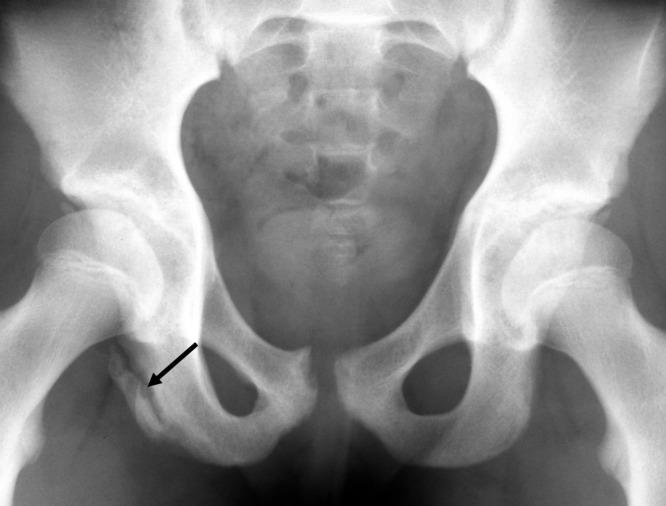

Peri-epiphyseal and Overuse Injuries in Adolescent Athletes.

RESULTS

Adolescent athletes can sustain physeal and bony stress injuries. Recovery and return to play occur more swiftly if such injuries are diagnosed early and immobilized until the patient is pain-free, typically about 4 weeks for apophyseal and epiphyseal overuse injuries. Certain epiphyseal injuries have prolonged symptoms with delayed treatment, including those involving the bones in the hand, elbow, and foot. If such injuries are missed, prolonged healing and significant restrictions in athletic pursuits may occur.

Some of these injuries are common to all weightbearing sports and are therefore widely recognized. Several are common in gymnastics but are rarely seen in other athletes. Early recognition and treatment of these conditions lead to quicker recovery and so may prevent season-ending, even career-ending, events from occurring.